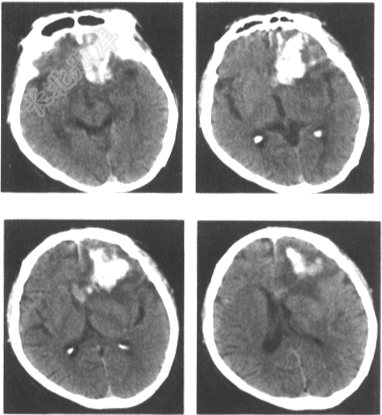

- 单项选择题男,47岁,外伤后CT检查所见如下图,最可能的诊断是

A、胶质瘤

B、钙化灶

C、脑膜瘤

D、脑出血

E、脑转移瘤